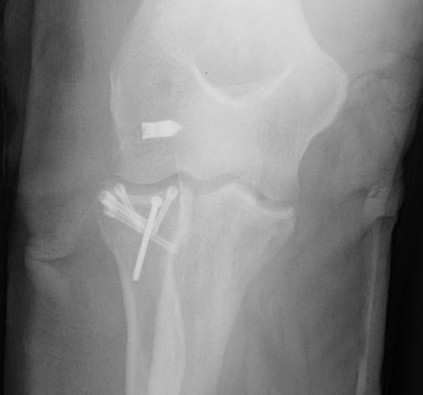

2. Elbow Dislocation

Terrible triad: radial head fracture, coronoid fracture, LCL injury

Radial Head Fixation

Indication

Significant fragment displacement

Reconstructable

Technique

Identify safe zone for implants

- posterolateral portion of cartilage / yellow and thinner, non articulating cartilage

- 90o arc between radial styloid and Lister's tubercle

- 2.5 or 3.5 headless compression screws

Complications

PIN injury

Intra-articular screws

Hardware failure

Heterotopic ossification

AVN

Non union

Radial head fragment nonunion

Results

Outcomes

- 56 patients with ORIF radial head

- 30 Mason 2, 26 Mason 3

- 13/14 patients with comminuted Mason 3 with > 3 fragments had poor outcome

- 15/15 patients with simple Mason 2 had good outcomes

- best results with 3 or fewer fragments